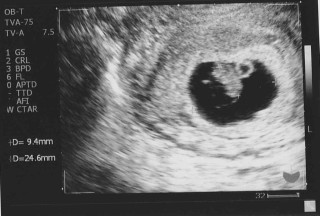

初めて病院に行った時の写真です!

この時は見てもまだ何が何だかよくわかりませんでしたが、心拍の確認をして生命ってすごいなぁとしみじみと感じました。

CRLは5.7mmでした。